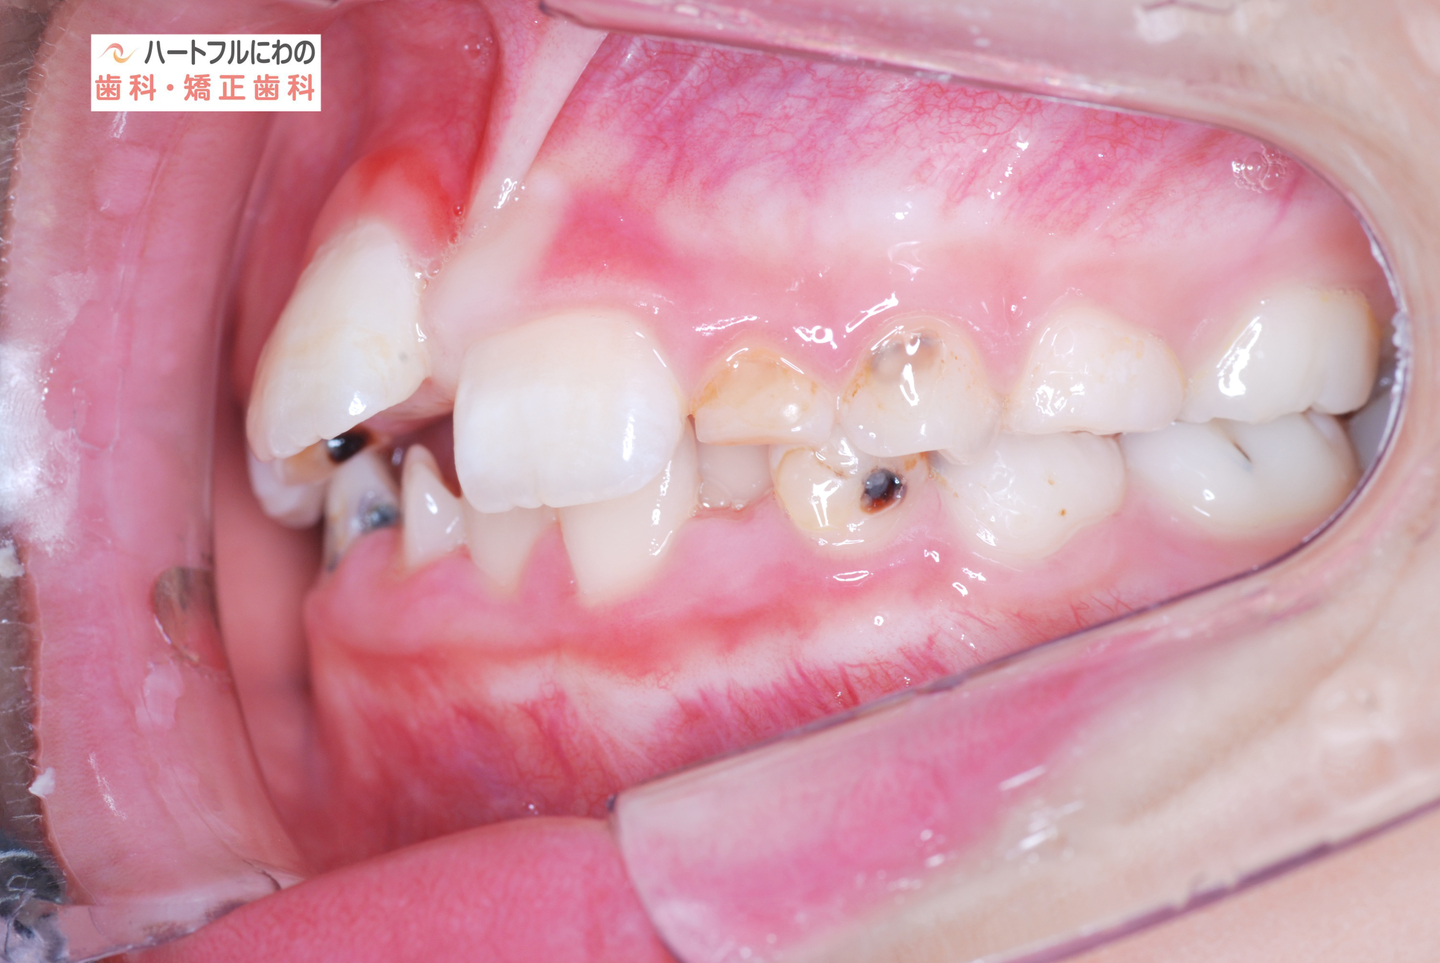

お口の中を拝見すると、上下の叢生(いわゆるガタガタ、乱ぐい)がみられ、多数の虫歯と歯肉炎がみられました。上唇小帯(上唇のすじ)の問題もありました。口呼吸で口腔内が乾燥すると通常の何倍も歯垢が付きやすくなり、虫歯や歯肉炎が頻発します。口呼吸の強い子は重なっている部分のかみ合わせが深い(下の歯がほとんどみえない)のもよく見られる特徴です。

奥歯と前歯の前後的位置関係は大きく改善し、正常になりました。